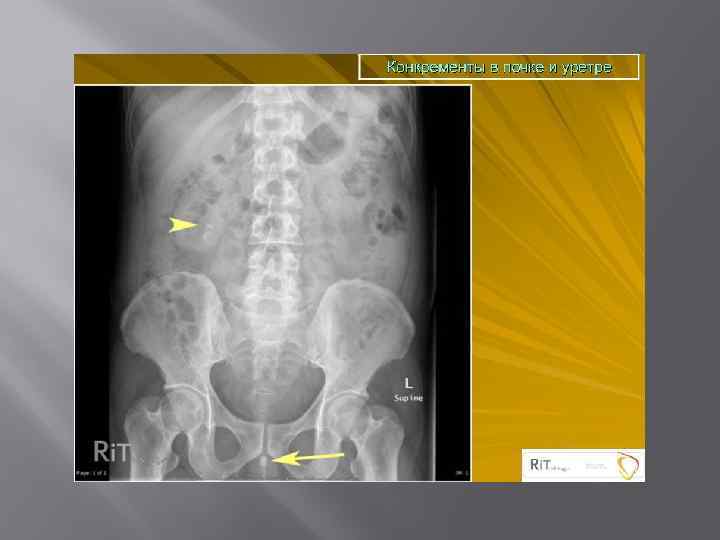

Мочекаменная болезнь ХРОНИЧЕСКИ ПРОТЕКАЮЩЕЕ ЗАБОЛЕВАНИЕ ХАРАКТЕРИЗУЮЩЕЕСЯ НАЛИЧИЕМ В ПОЛОСТНОЙ СИСТЕМЕ ИЛИ ПАРЕНХИМЕ КАМНЕЙ, ФОРМИРУЮЩИХСЯ ИЗ СОСТАВНЫХ ЧАСТЕЙ МОЧИ. Составляют 30 -40% всех хирургических заболеваний. Различают одиночный камень, множественные лоханочные и комбинации лоханочного камня с чашечковым или поренхиматозными. Выделяют понятие рентгенонегативного камня, т. е. камень который не даёт тени на рентгенограмме.

Экскреторная урография -рентгненегативные камни- дефект наполнения - Рентгенпозитивные камни-тень камня усиливается

Уролитиаз Камни чашечек

Коралловидные камни